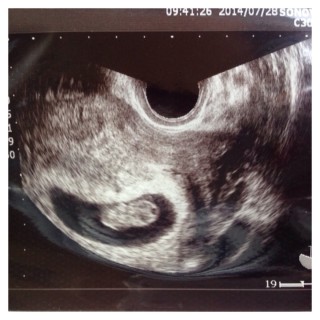

9w2d。 初めての妊娠(*^^*) 新婚旅行の2日前にわかりました❗(笑) もう可愛くて可愛くて仕方ないです(^o^)🍀 次の検診待ち遠しいo(^o^)o

2週間前に8wぐらいの大きさだと言われたのですが、本日9w2dで出産予定日確定しました☆心当たりのある日から自分で計算した週数とも合ってました(´ω`)次回は3週間後です!

基礎体温・排卵検査薬では8w4dの計算だったのですが、本日予定日確定して、9w2dみたいです! 順調な様で母子手帳の手続きも出来て、まだ夢みたいでしたが少し実感が出てきました^ ^ 次は2週間後待ちきれません(。-_-。)